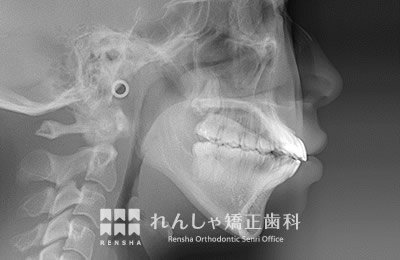

大人

軽度の上顎前突であれば、上奥歯の後方移動で前歯の前突を改善することもありますが、上顎前突は叢生の問題も絡んでいることがほとんどで、永久歯の抜歯が必要になることがあります。また上奥歯の後方移動には矯正矯正用アンカースクリューの併用が効果的です。

| 主訴 | 出っ歯と前歯のがたつき |

|---|---|

| 診断名 | Angle Class II 上顎前突 |

| 初診時年齢 | 20歳7か月 |

| 装置名 | マルチブラケット装置 矯正用アンカースクリュー |

| 抜歯非抜歯 | 上下顎左右第二小臼歯の抜歯(合計4本) |

| 治療期間 | 3年2か月 |

| 費用の目安 | 約75万円+消費税(検査料金、都度の処置費用等も合わせた総額) |

| リスク副作用 | 歯の移動に伴う軽微な歯根吸収、歯槽骨吸収、歯肉退縮(本症例では軽度の歯肉退縮と歯根吸収を認めた)、矯正器具装着中のカリエスリスク増大(本症例では大臼歯にカリエスが発生し、その後う蝕処置)、上顎左側犬歯の失活 |